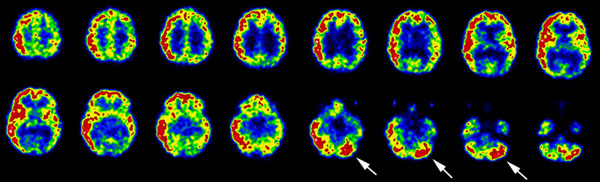

findings. Imaging

o

On scintigraphic examination

·

early subacute thyroiditis there is

typically poor visualization of the entire thyroid. Single or multiple

hypofunctioning areas are occasionally seen as the disease can be focal and

present as a cold area/nodule.

Increased radioactive iodine uptake is seen

during the hypothyroid phase (late) of the disease.